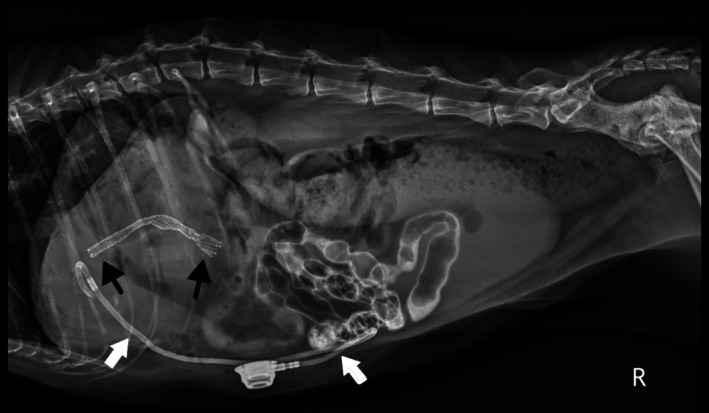

Post‐operative radiographs confirmed appropriate placement of the stent and the biliary drainage catheter (Figure 2). Abdominal ultrasonography showed asymmetric biliary tract decompression, with persistent right‐sided intrahepatic biliary tract dilatation (Figure 3A) and resolved left intrahepatic biliary tract dilatation (Figure 3B). The stent was visualized extending from the duodenal lumen through the CBD and into the left lateral liver lobe within the biliary tract (Figure 3C). A large volume of echogenic peritoneal effusion also was observed with hyperechoic mesenteric fat. Fluid analysis was consistent with mild mixed inflammation; no bacteria were seen; aerobic and anaerobic cultures were negative.

Improvement of hyperbilirubinemia and increased liver enzyme activities was noted post‐operatively (Table S1). Post‐operative radiographs showed an appropriately‐placed stent and biliary drainage tube (see Figure 5). A partial kink of the tubing was seen as it entered the body wall, but it was of no clinical consequence. Ultrasonography showed asymmetrical decompression of the intrahepatic biliary duct tracts, with ongoing right biliary obstruction and left‐sided decompression (Figure 6). Echogenic peritoneal effusion and hyperechogenicity of the cranial mesenteric fat also were noted.